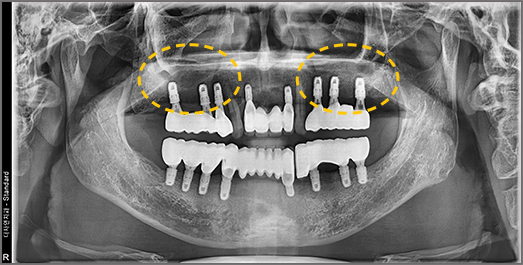

전체 임플란트

전체적으로 치아를 회복하기 위한 임플란트

치아의 기능을 다시 회복하기 위해

선택하는 임플란트입니다. 상실한 치아를 오랫동안 방치한 경우

상, 하악 잇몸뼈의 양도 부족한 경우가 많기 때문에 개개인의 건강 상태를 고려하여

정확한 수술 계획을 세워야 합니다.

• BEFORE: 2022.12.15

• AFTER: 2023.02.23